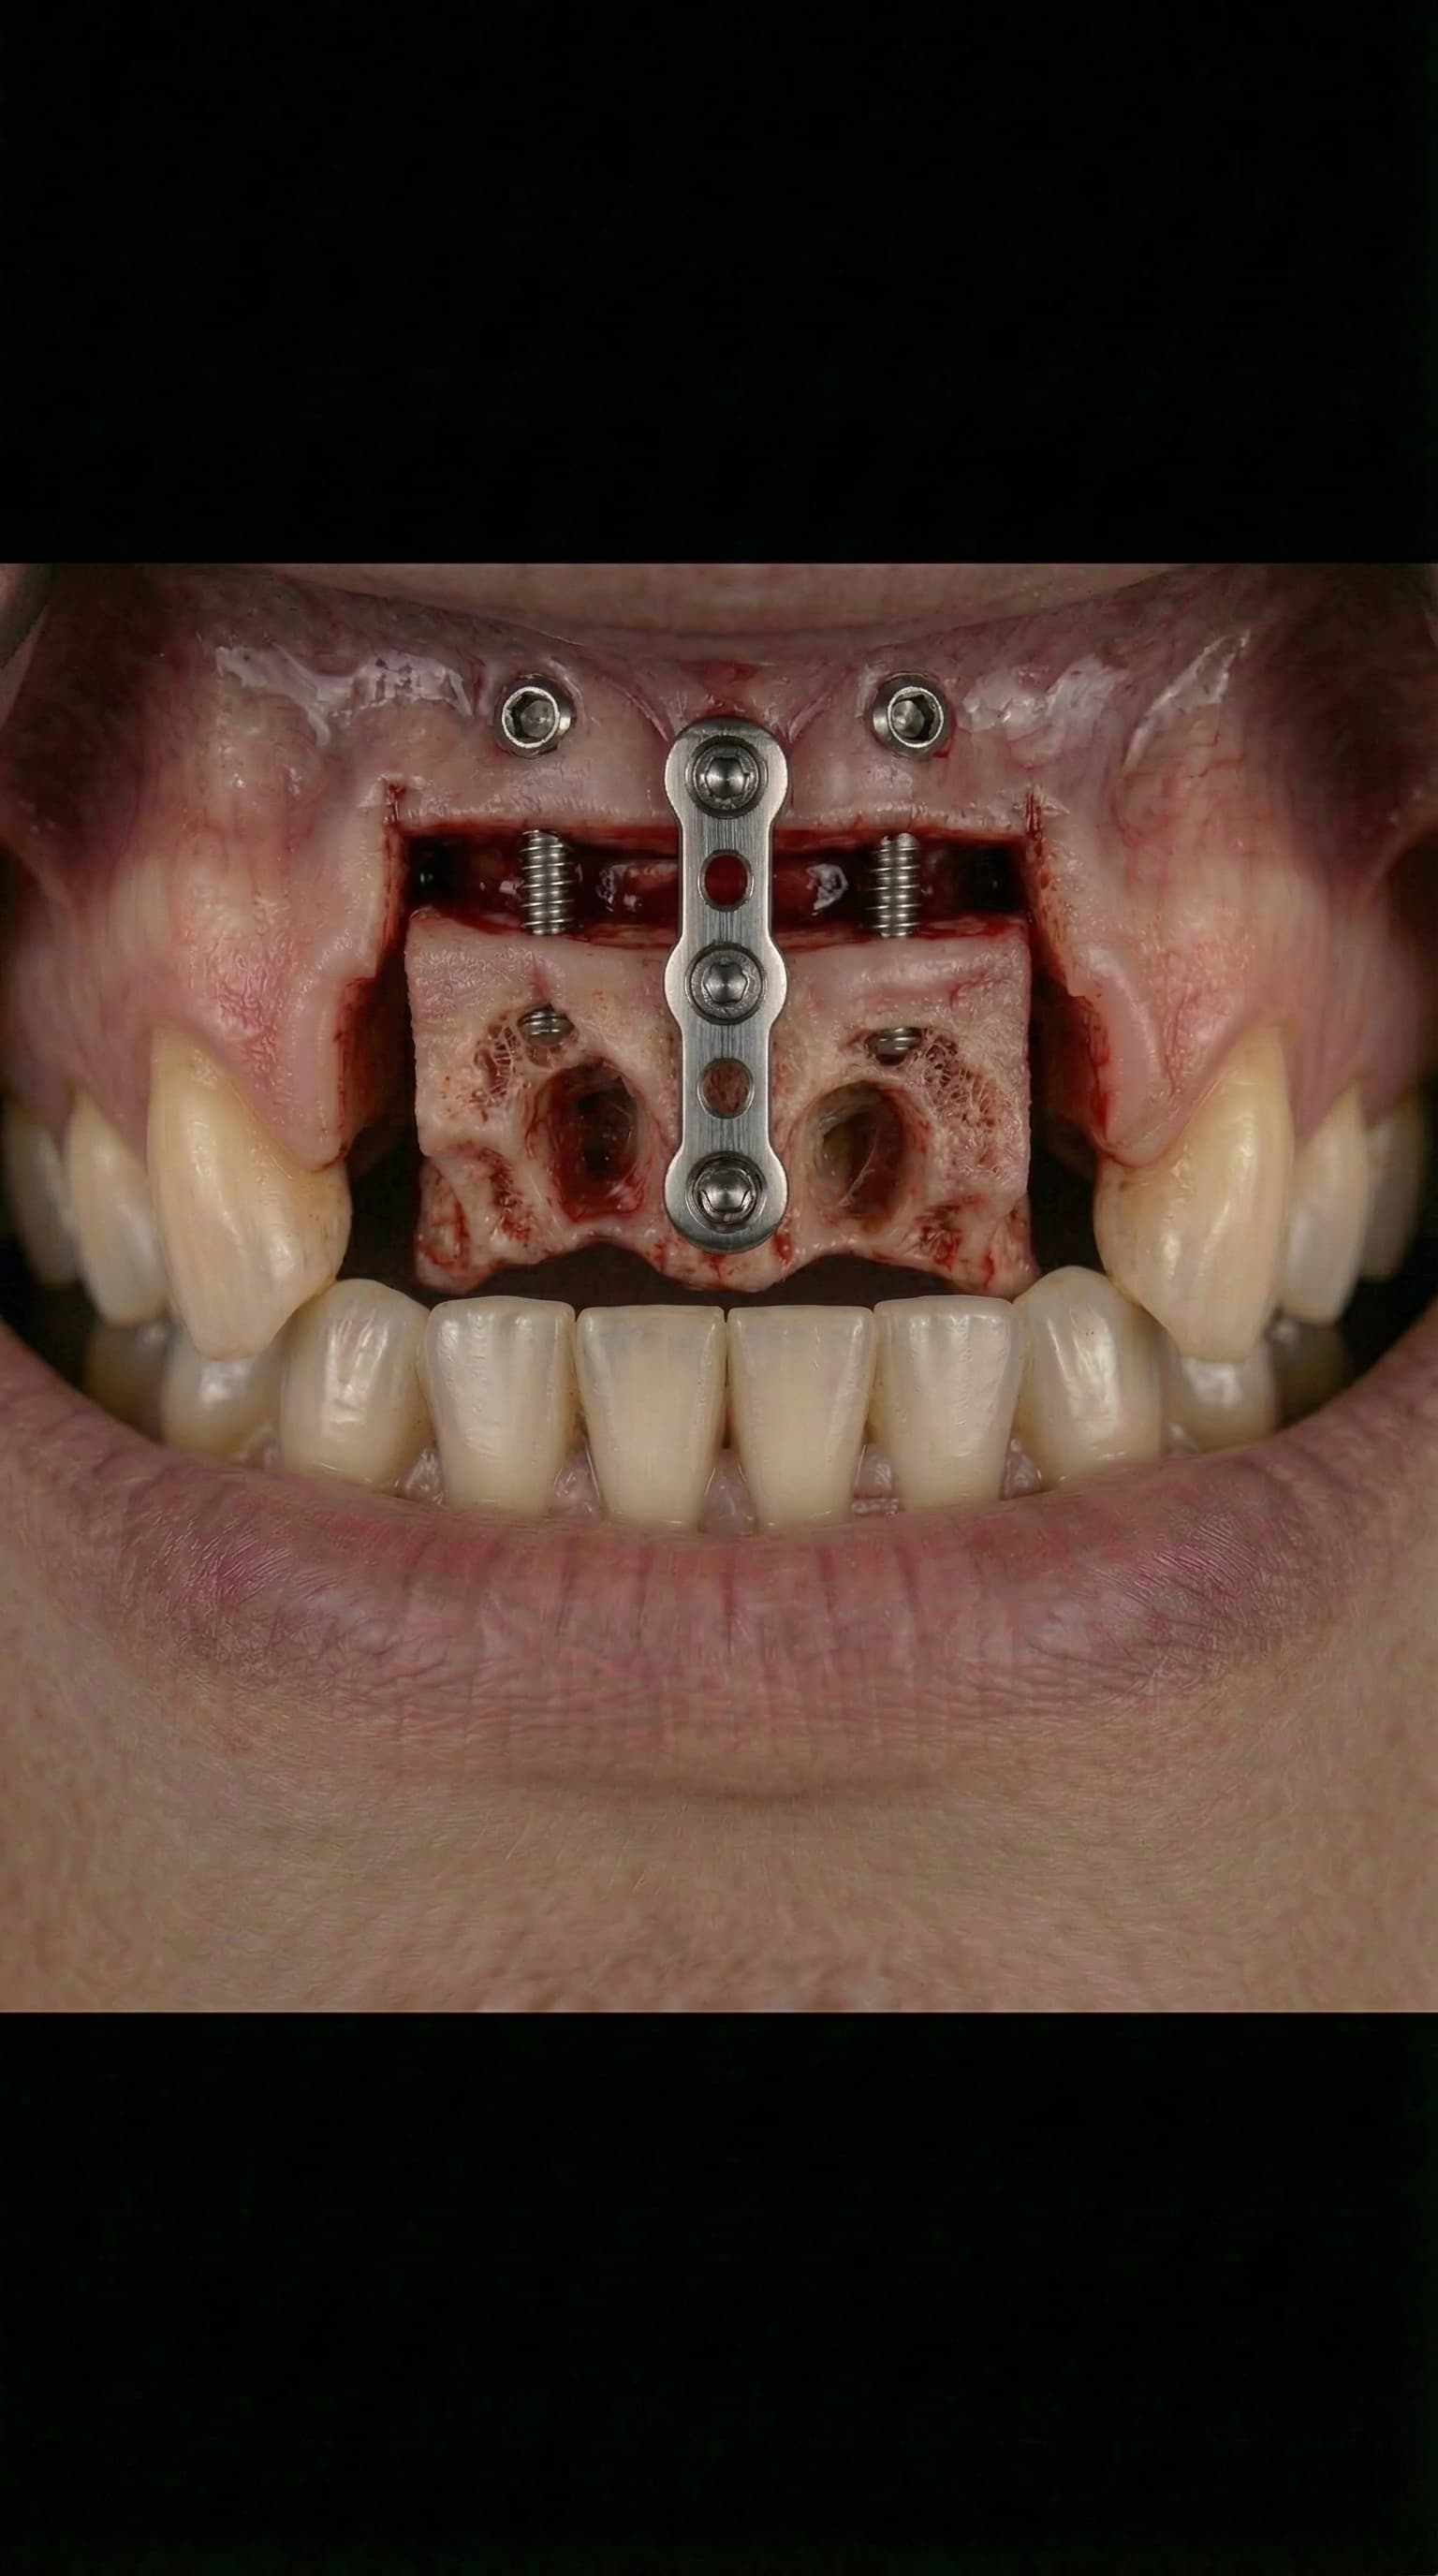

Bone Grafting & Sinus Lifts

Advanced bone regeneration using organic and holistic bone grafting materials to rebuild jawbone lost to tooth extraction, periodontal disease, or trauma. Dr. Antipov performs sinus lift surgery (sinus augmentation), ridge augmentation, socket preservation, block bone grafts, and guided bone regeneration (GBR). We offer autogenous (your own bone), allograft, xenograft, and synthetic bone graft options — including minimally processed, naturally derived materials for patients who prefer a holistic approach to dental implant preparation.